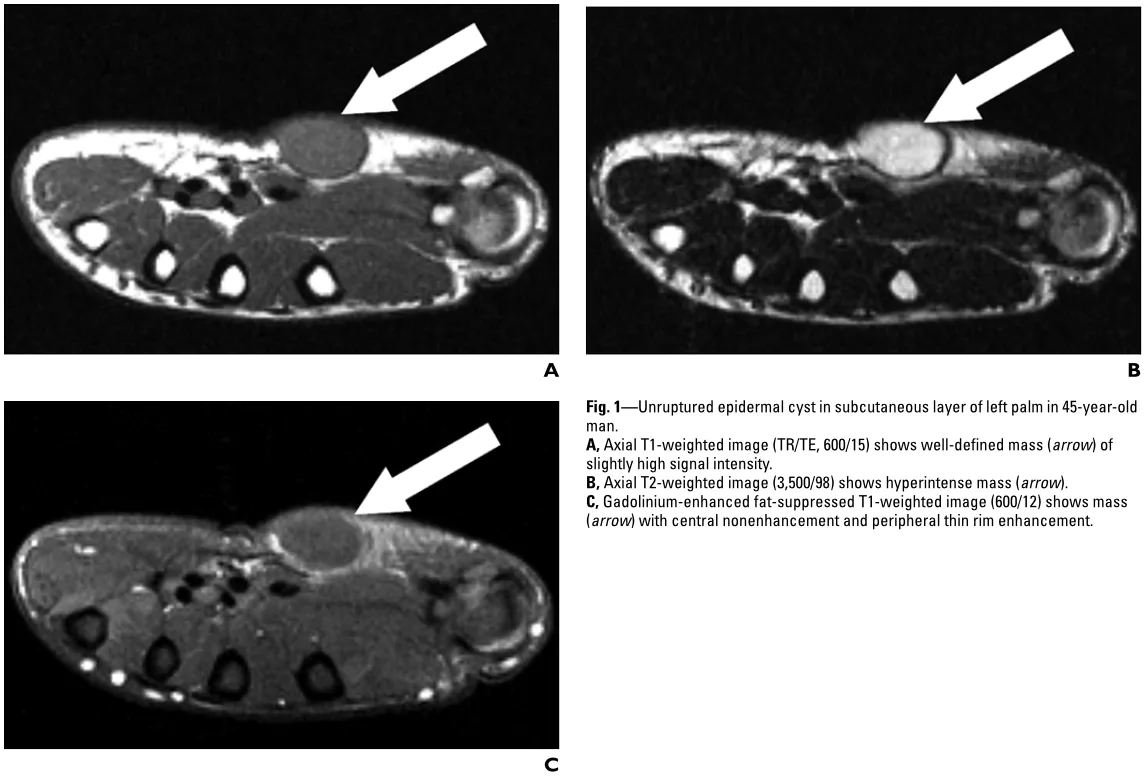

今回は手部に生じた表皮嚢腫の摘出手術でした.

手に生じた表皮囊腫のMRI.

引用元:Hong SH. MRI Findings of subcutaneous epidermal cysts: Emphasis on the presence of rupture. AJR Am J Roentgenol. 2006. 186.

1年前からあったせいか, 炎症の影響で嚢腫は周囲組織と強く癒着しており, 指神経や血管を丁寧に剥離しながら慎重に操作を進めました.